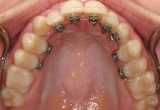

Τα γλωσσικά σιδεράκια τοποθετούνται στην εσωτερική επιφάνεια των δοντιών με αποτέλεσμα να ικανοποιούνται όλες οι αισθητικές ανάγκες ακόμα και του πιο απαιτητικού ασθενή.